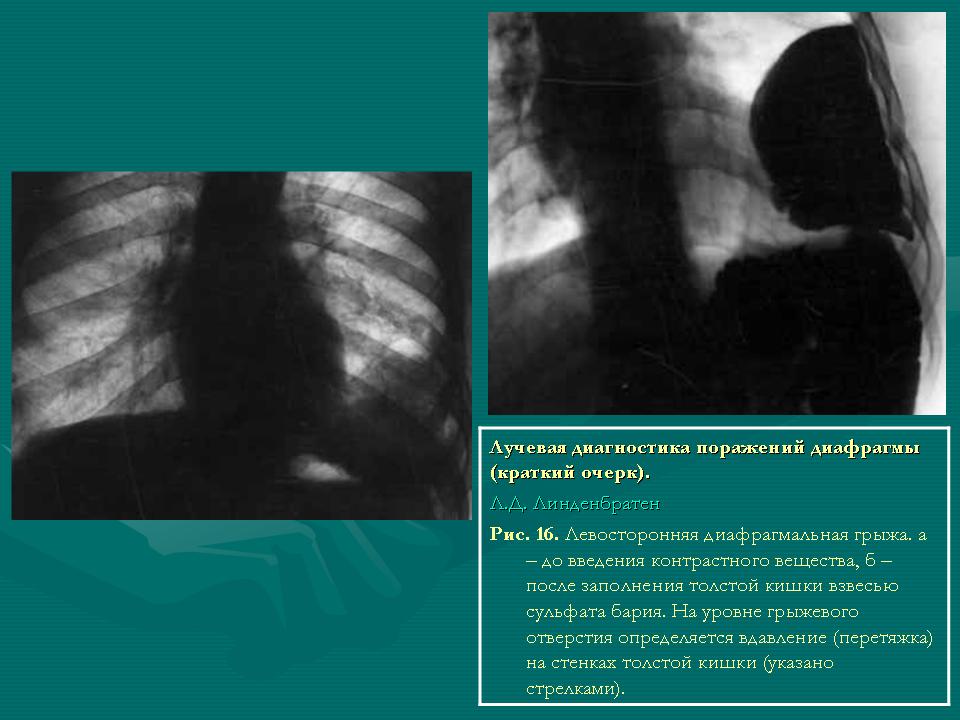

Главным признаком как истинной, так и ложной диафрагмальной грыжи (трансдиафрагмального пролапса), определяемым при всех лучевых методах, служит появление в грудной полости необычного образования, неотделимого от диафрагмы. Оно четко отграничено от легочной ткани, если нет плевральных наслоений. Структура тени образования зависит от состава грыжи. В ней может оказаться любой орган живота; с убывающей частотой в грыже находятся толстая кишка, тонкая кишка, желудок, сальник, селезенка, почка, печень. Соответственно на рентгенограммах и компьютерных томограммах в грудной полости обнаруживаются либо петли кишок, содержащие газ и тени пищевых масс, либо раздутый газом желудок (с горизонтальным уровнем жидкости), либо однородная тень паренхиматозного органа (рис. 15). С наличием кишечных петель связан другойважный симптом грыжи – изменчивость рентгеновской картины на повторных снимках. Меняются число, положение и величина газовых пузырей, перегородок между ними, количество содержимого. Такие же изменения можно заметить при перемене положения тела. Весьма опасно ущемление такой грыжи. Распознавание этого осложнения базируется на клинических признаках кишечной непроходимости и рентгеновских симптомах. В грудной полости определяются раздутые газом петликишок с горизонтальными уровнями жидкости. Приводящая часть кишечника, находящаяся в брюшной полости, тоже вздута, а отводящая часть находится в спавшемся состоянии. Вообще диафрагмальную грыжу следует рассматривать как тяжелое заболевание, даже если в период лучевого исследования оно протекает малосимптомно. Надо рекомендовать пациенту (а если это ребенок, то родителям)иметь в документе записку с несложным текстом: “У меня диафрагмальная грыжа”. В случае ущемления грыжи это решающим образом поможет диагностике и облегчит проведение операции.Ценные сведения доставляет контрастирование пищевода и кишечника. При этом подтверждается существование грыжи или пролапса, уточняется их содержимое и устанавливаются положение и величина грыжевых ворот, поскольку на уровне грыжевого отверстия обнаруживаются вдавления на стенках желудка или кишки (рис. 16). Грыжа травматического происхождения может располагаться в любом отделе диафрагмы (рис. 17). Изза воспалительных или рубцовых изменений ее дыхательная подвижность отсутствует или ограничена; иногда заметны парадоксальные движения. Вне зоны повреждения подвижность диафрагмы ограничена. Большое выпячивание вызывает смещение средостения и ведет к нарушению дыхательной и сердечной деятельности. Истинные диафрагмальные грыжи бывают врожденными и приобретенными. Первые связаны с аномалией развития диафрагмы и составляют большинство грыж у детей. По средством ультразвукового исследования или МРТ они могут быть найдены даже в пренатальном периоде с одновременной оценкой их влияния на легочные объемы. Приобретенные грыжи могут локализоваться в любой части диафрагмы. Но к типичным вариантам грыж относятся: 1) грыжа при аплазии половины диафрагмы; 2) грыжа при аплазии грудинной части диафрагмы; 3) грыжа в области грудинореберного треугольника; 4) грыжа в области поясничнореберного треугольника; 5) грыжа пищеводного отверстия диафрагмы (в данной статье не рассматривается).